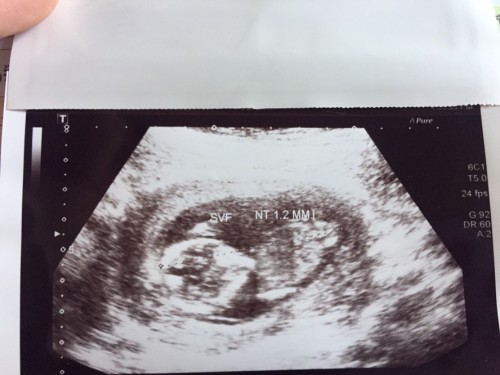

18 wks แล้วลูก ขอให้หนูแข็งแรงนะ

quadruple test ปกติ แม่กับพ่อก็โล่งอกแล้วลูกรัก